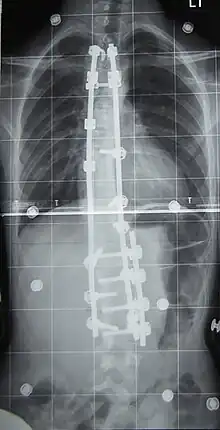

Surgery

Surgery is usually recommended by orthopedists for curves with a high likelihood of progression (i.e., greater than 45 to 50° of magnitude), curves that would be cosmetically unacceptable as an adult, curves in people with spina bifida and cerebral palsy that interfere with sitting and care, and curves that affect physiological functions such as breathing.[50]

Surgery is indicated by the Society on Scoliosis Orthopaedic and Rehabilitation Treatment (SOSORT) at 45 to 50°[4] and by the Scoliosis Research Society (SRS) at a Cobb angle of 45°.[51] SOSORT uses the 45 to 50° threshold as a result of the well-documented, plus or minus 5° measurement error that can occur while measuring Cobb angles.

Surgeons who are specialized in spine surgery perform surgery for scoliosis. To completely straighten a scoliotic spine is usually impossible, but for the most part, significant corrections are achieved.[52]

The two main types of surgery are:

- Anterior fusion: This surgical approach is through an incision at the side of the chest wall.

- Posterior fusion: This surgical approach is through an incision on the back and involves the use of metal instrumentation to correct the curve.

One or both of these surgical procedures may be needed. The surgery may be done in one or two stages and, on average, takes four to eight hours.